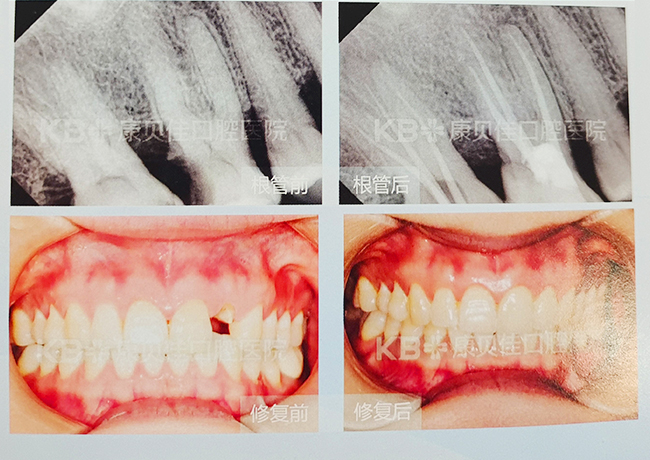

陈女士 65岁

左上前牙假牙脱落。患者一年多前在外院做过左上侧切牙桩冠修复,左上中切牙根管治疗。因侧切牙桩核脱落,前来我院就诊。取模翻制临时冠模型,拍术前照片。清理龋坏牙体组织,根管桩道清理,消毒,牙龈修整,排龈,3M纤维桩+树脂核,21牙体粗制备,戴临时冠。